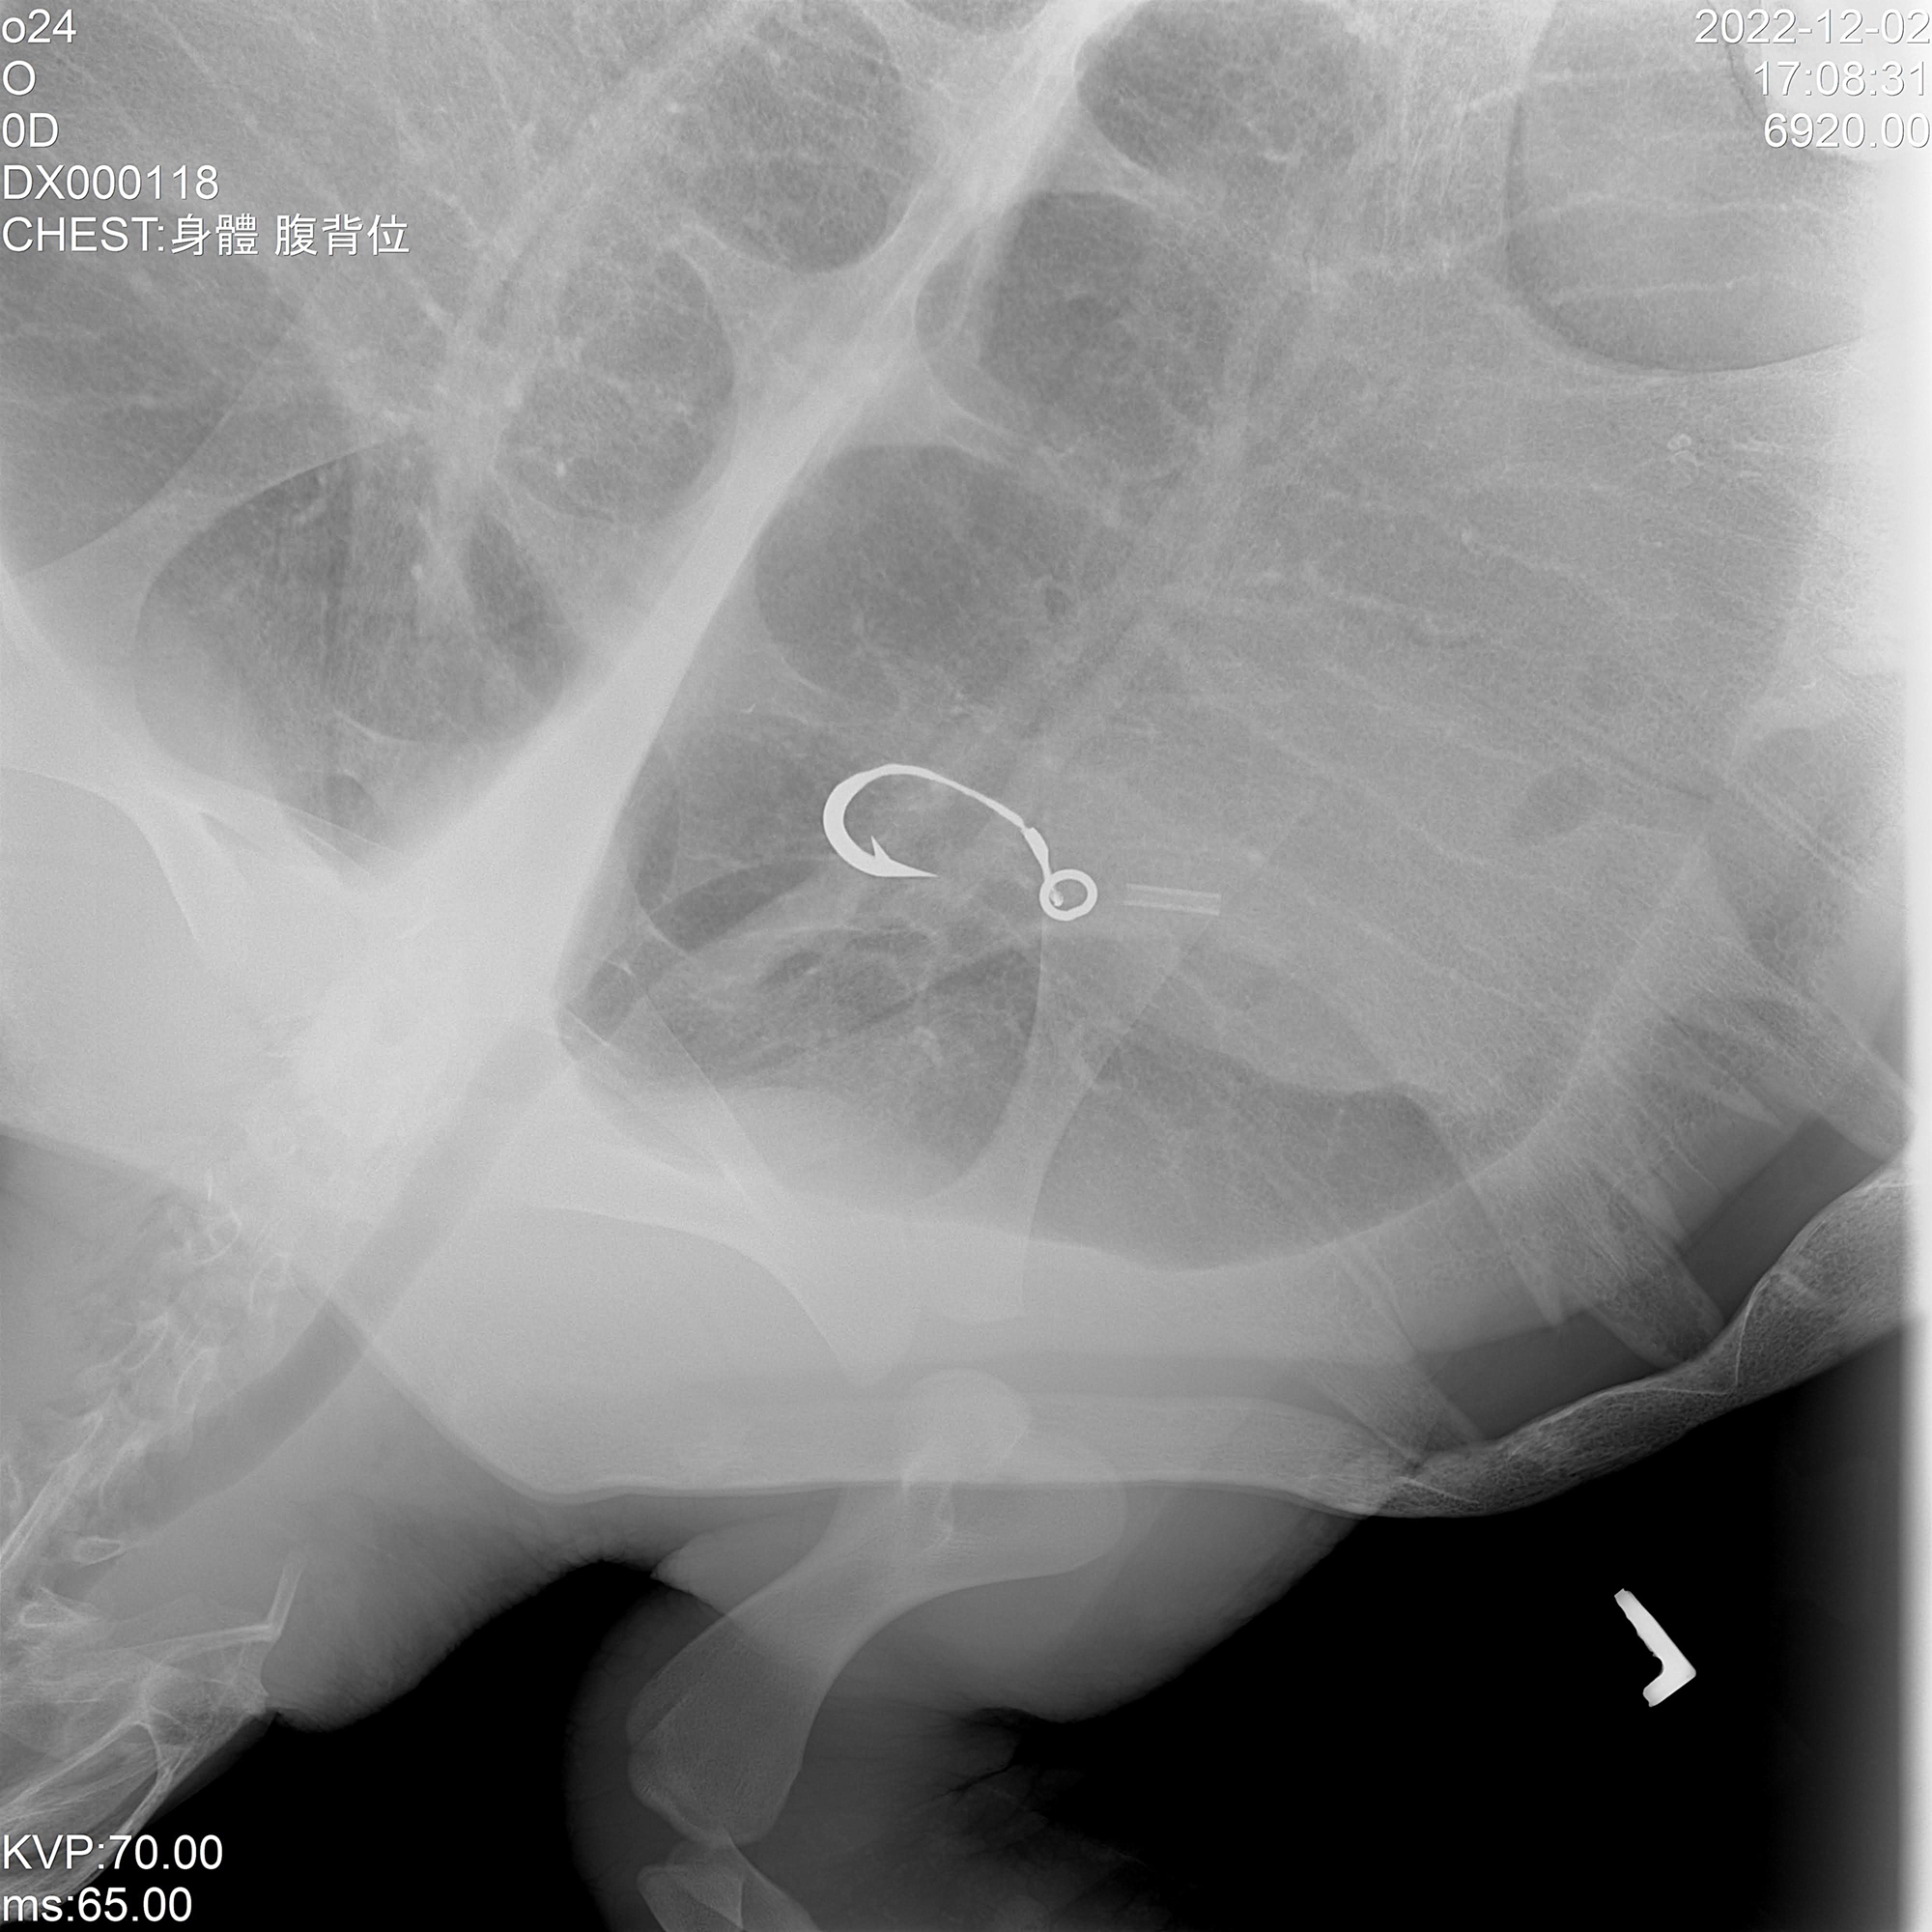

Improperly discarded fish hooks may be eaten by sea turtles, causing serious injury. (courtesy of OCA)

Li says: “In the process of rescuing and sheltering turtles, we see the kinds of threats they face.” Mistakenly ingested plastic garbage or fishing hooks tell of the damage that humankind is doing to the sea. Decreasingly effective antibiotics indicate that the development of resistance to medications is no longer limited to people. Fibropapillomatosis, a debilitating neoplastic disease whose cause is as yet uncertain but is currently thought to be associated with chelonid herpesvirus 5 (ChHV5), constitutes another threat to sea turtles.